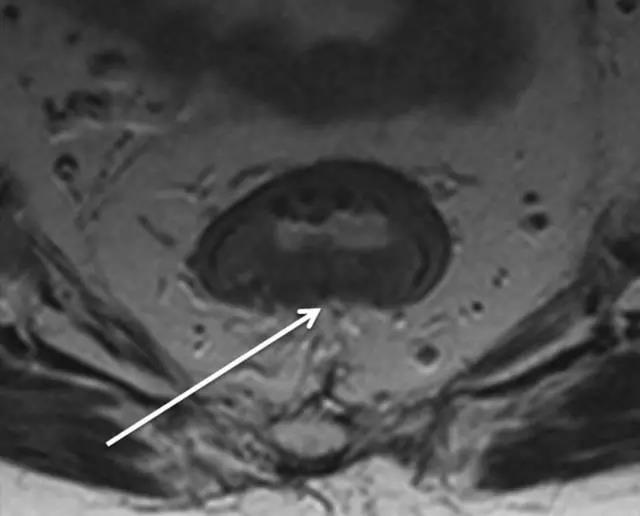

62 岁直肠癌男性,T2 加权轴位图像显示 T2 期,环形肿瘤侵犯但未超过肌层。